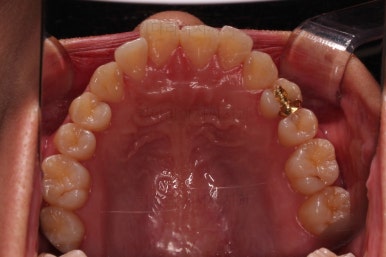

초진 시 입안의 모습입니다.

치열이 많이 삐뚠 것은 아니지만 앞니쪽이 삐뚤어 있고요. 아랫니 사이사이에 고루 틈새가 있네요.

윗니는 삐뚤고(공간부족), 아랫니는 틈새가 있다면(공간 과잉) 그 부조화는 부정교합을 의미합니다.